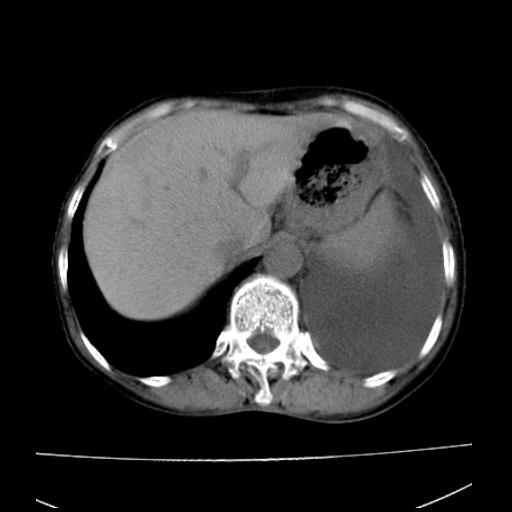

以下是引用随光逐影在2010-3-24 19:15:00的发言:[br]结合病史,考虑双肺及纵隔淋巴结多发转移、左侧胸膜转移并左侧大量胸水,左下肺膨胀不全。

以下是引用zxl51642在2010-3-24 18:49:00的发言:[br]结合乳腺癌术后病史,考虑双肺及纵隔淋巴结多发转移、左侧胸膜转移并左侧大量胸水、左下肺膨胀不全。